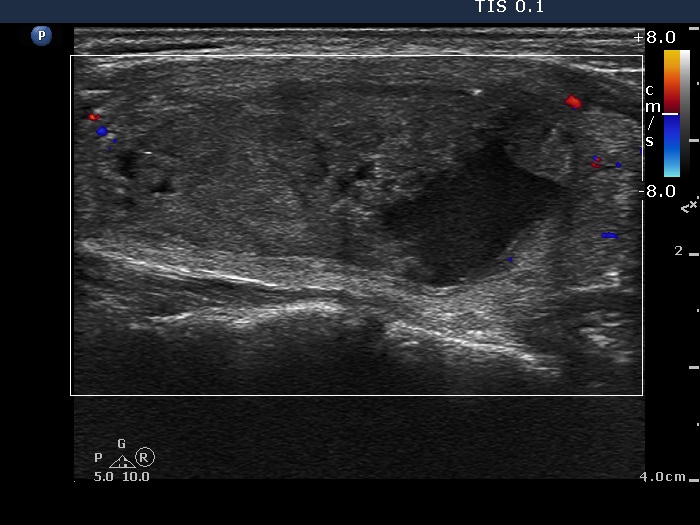

Ethanol sclerotherapy: other examples - Case 3: treatment of a gelatinous thyroid cyst

Third session of therapy (ultrasonographic picture 3)

Right lobe, longitudinal section, color Doppler mode. No signs of blood flow.